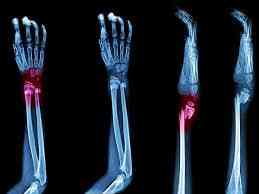

Causes of bone fracture

What causes bone fractures? Bone fractures are almost always caused by traumas. Anything that hits one of your bones with enough force can break it. Some of the most common causes include: Car accidents. Falls. Sports injuries.